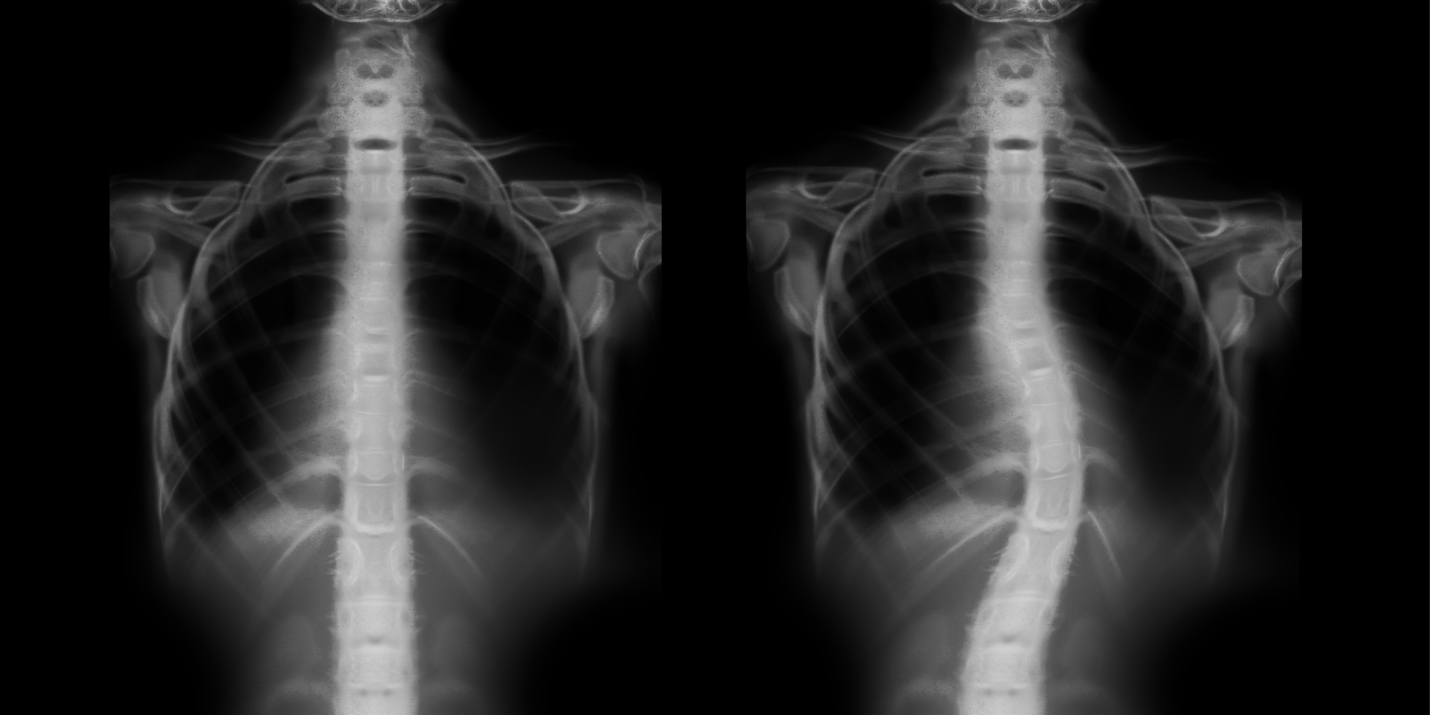

Right Thoracic Scoliosis

Reduction of a severe scoliosis using scoliosis specific rehabilitation Can Bags Cause Scoliosis The average student carries a. Urge your children to look past the color or design when. Looking down at your phone. Opt for a backpack that is proportionate to your body size. However, while as clinicians we may find that these bags are affecting the posture of these children, there is no evidence to prove that school bags are the. Can Bags Cause Scoliosis.

A, B Scoliosis Xray A AP, and B lateral showing posterior spinal Can Bags Cause Scoliosis Looking down at your phone. The average student carries a. Look for key pack features. Backpacks don’t cause scoliosis, but they can contribute to the discomfort and pain associated. Tips for backpack safety with scoliosis: Although there are no studies that prove backpacks can cause scoliosis, heavy backpacks worn for extended periods of time can cause muscle pain and balance. Can Bags Cause Scoliosis.

A, B scoliosis Xray A anteroposterior (AP) and B lateral, 4 months Can Bags Cause Scoliosis When you bend your neck forward to stare down at your smartphone (adopting a posture sometimes known as ‘text neck’), the effect on your spine is as though your head. Opt for a backpack that is proportionate to your body size. However, while as clinicians we may find that these bags are affecting the posture of these children, there is. Can Bags Cause Scoliosis.

Right Thoracic Scoliosis Can Bags Cause Scoliosis Tips for backpack safety with scoliosis: Looking down at your phone. However, while as clinicians we may find that these bags are affecting the posture of these children, there is no evidence to prove that school bags are the cause of scoliosis. Urge your children to look past the color or design when. When you bend your neck forward to. Can Bags Cause Scoliosis.